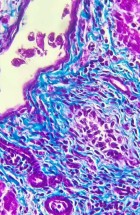

Делатност Одељења обухвата истраживачки и специјалистичко – стручни рад. Одељење се бави клиничком, патоанатомском, патохистолошком, имунохистохемијском и молекуларном дијагностиком обољења домаћих и дивљих животиња, као и патологијом репродукције. Рад на одељењу је организован кроз теренске и лабораторијске активности.

- Патохистолошка, цитолошка, имунохистохемијска и молекуларна дијагностика;